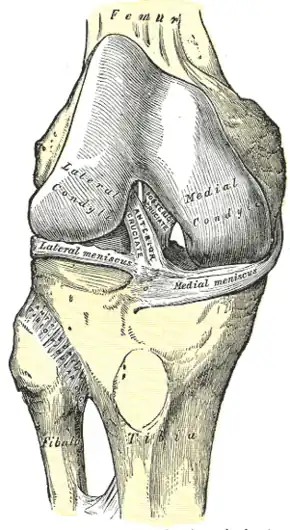

Right knee joint, from the front, showing interior ligaments

Right knee joint, from the front, showing interior ligaments -